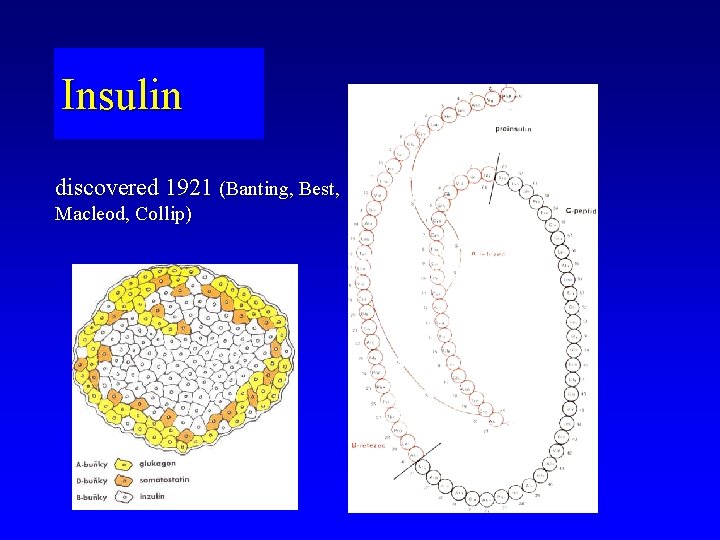

Insulin discovered 1921 (Banting, Best, Macleod, Collip)